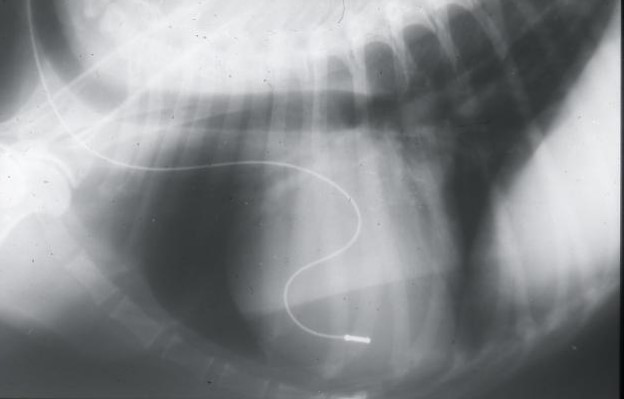

What does this show?

Pacing lead down jugular vena cava

Why should we use a sophisticated pacemakers?

Sophisticated pacemakers have been able to allow for increase in HR when exercising and decrease in HR when rest – a lot of them just do a fixed constant rate HR – better ones can change!